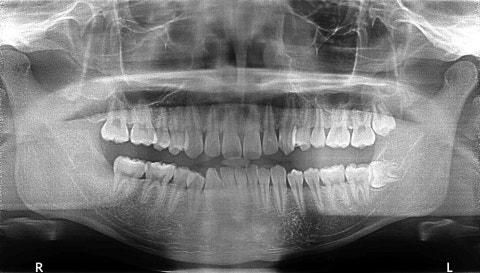

사각턱 수술 때문에 신경선 위치 좀 봐주세요

안면윤곽 하기에 신경선 위치가 많이 낮은 편인가요?ㅠㅠ

어디가 신경선인지 잘 모르겠어서요.ㅠㅠ 혹시 신경선 위치 좀 봐주실 수 있나요

• 1번 째 사진